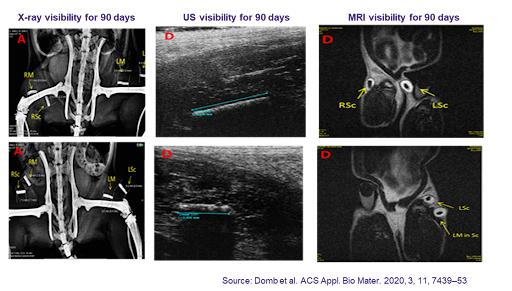

A fully resorbable marker, visible by Mammography, US and MRI for a predetermined period (3, 6, or 12 months).

Successfully tested on animals; remains visible for at least 4 months and fully biodegrades.